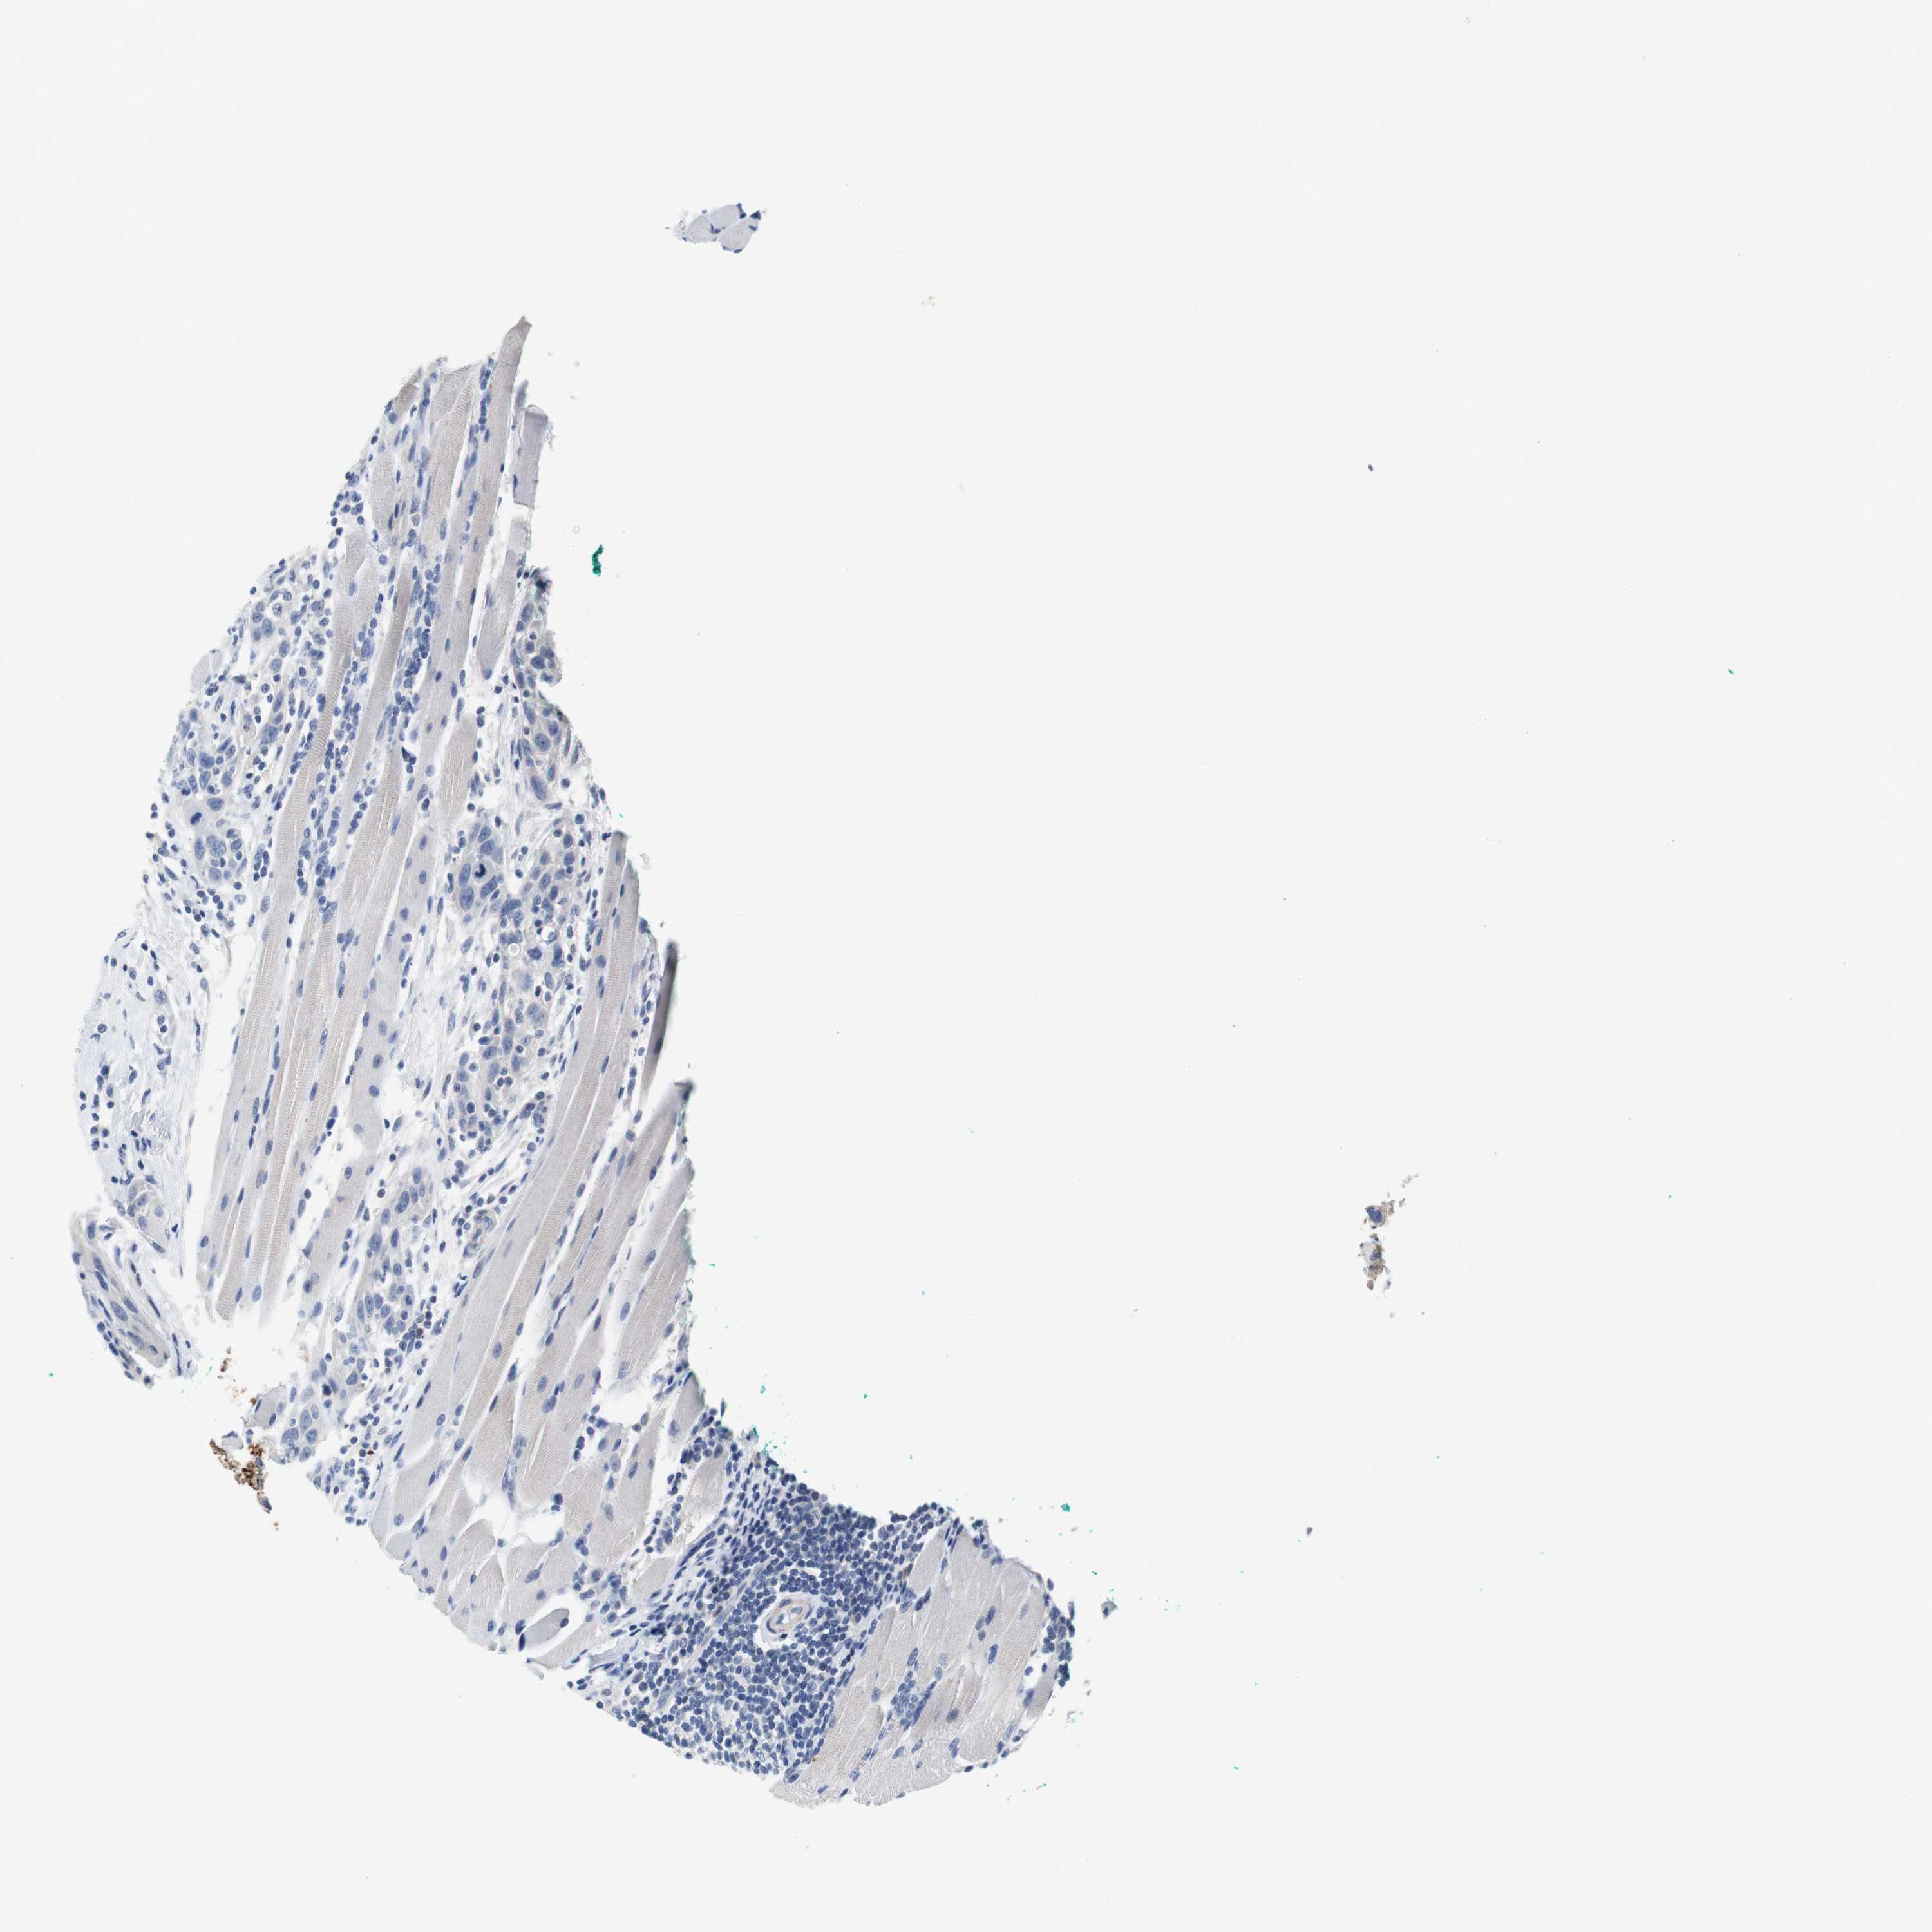

HEAD AND NECK CANCER - Protein expressioni

A mouse-over function shows sample information and annotation data. Click on an image to view it in a full screen mode. Samples can be filtered based on level of antibody staining by selecting one or several of the following categories: high, medium, low and not detected. The assay and annotation is described here.

Antibody stainingi

Antibody staining in the annotated cell types in the current human tissue is reported as not detected, low, medium, or high, based on conventional immunohistochemistry profiling in selected tissues. This score is based on the combination of the staining intensity and fraction of stained cells.

Each image is clickable and will lead to virtual microscopy that enables deeper exploration of all samples and also displays staining intensity scores, fraction scores and subcellular localization as well as patient and tissue information for each sample.

Antibody HPA006277

Antibody HPA006507

Antibody CAB017027

Staining

High

Medium

Low

Not detected

Intensity

Strong

Moderate

Weak

Negative

Quantity

>75%

75%-25%

<25%

None

Location

Nuclear

Cytoplasmic/membranous

Cytoplasmic/membranous,nuclear

Squamous cell carcinoma, NOS

Carcinoma, NOS

Adenocarcinoma, NOS

Squamous cell carcinoma, metastatic, NOS

Adenoma, NOS